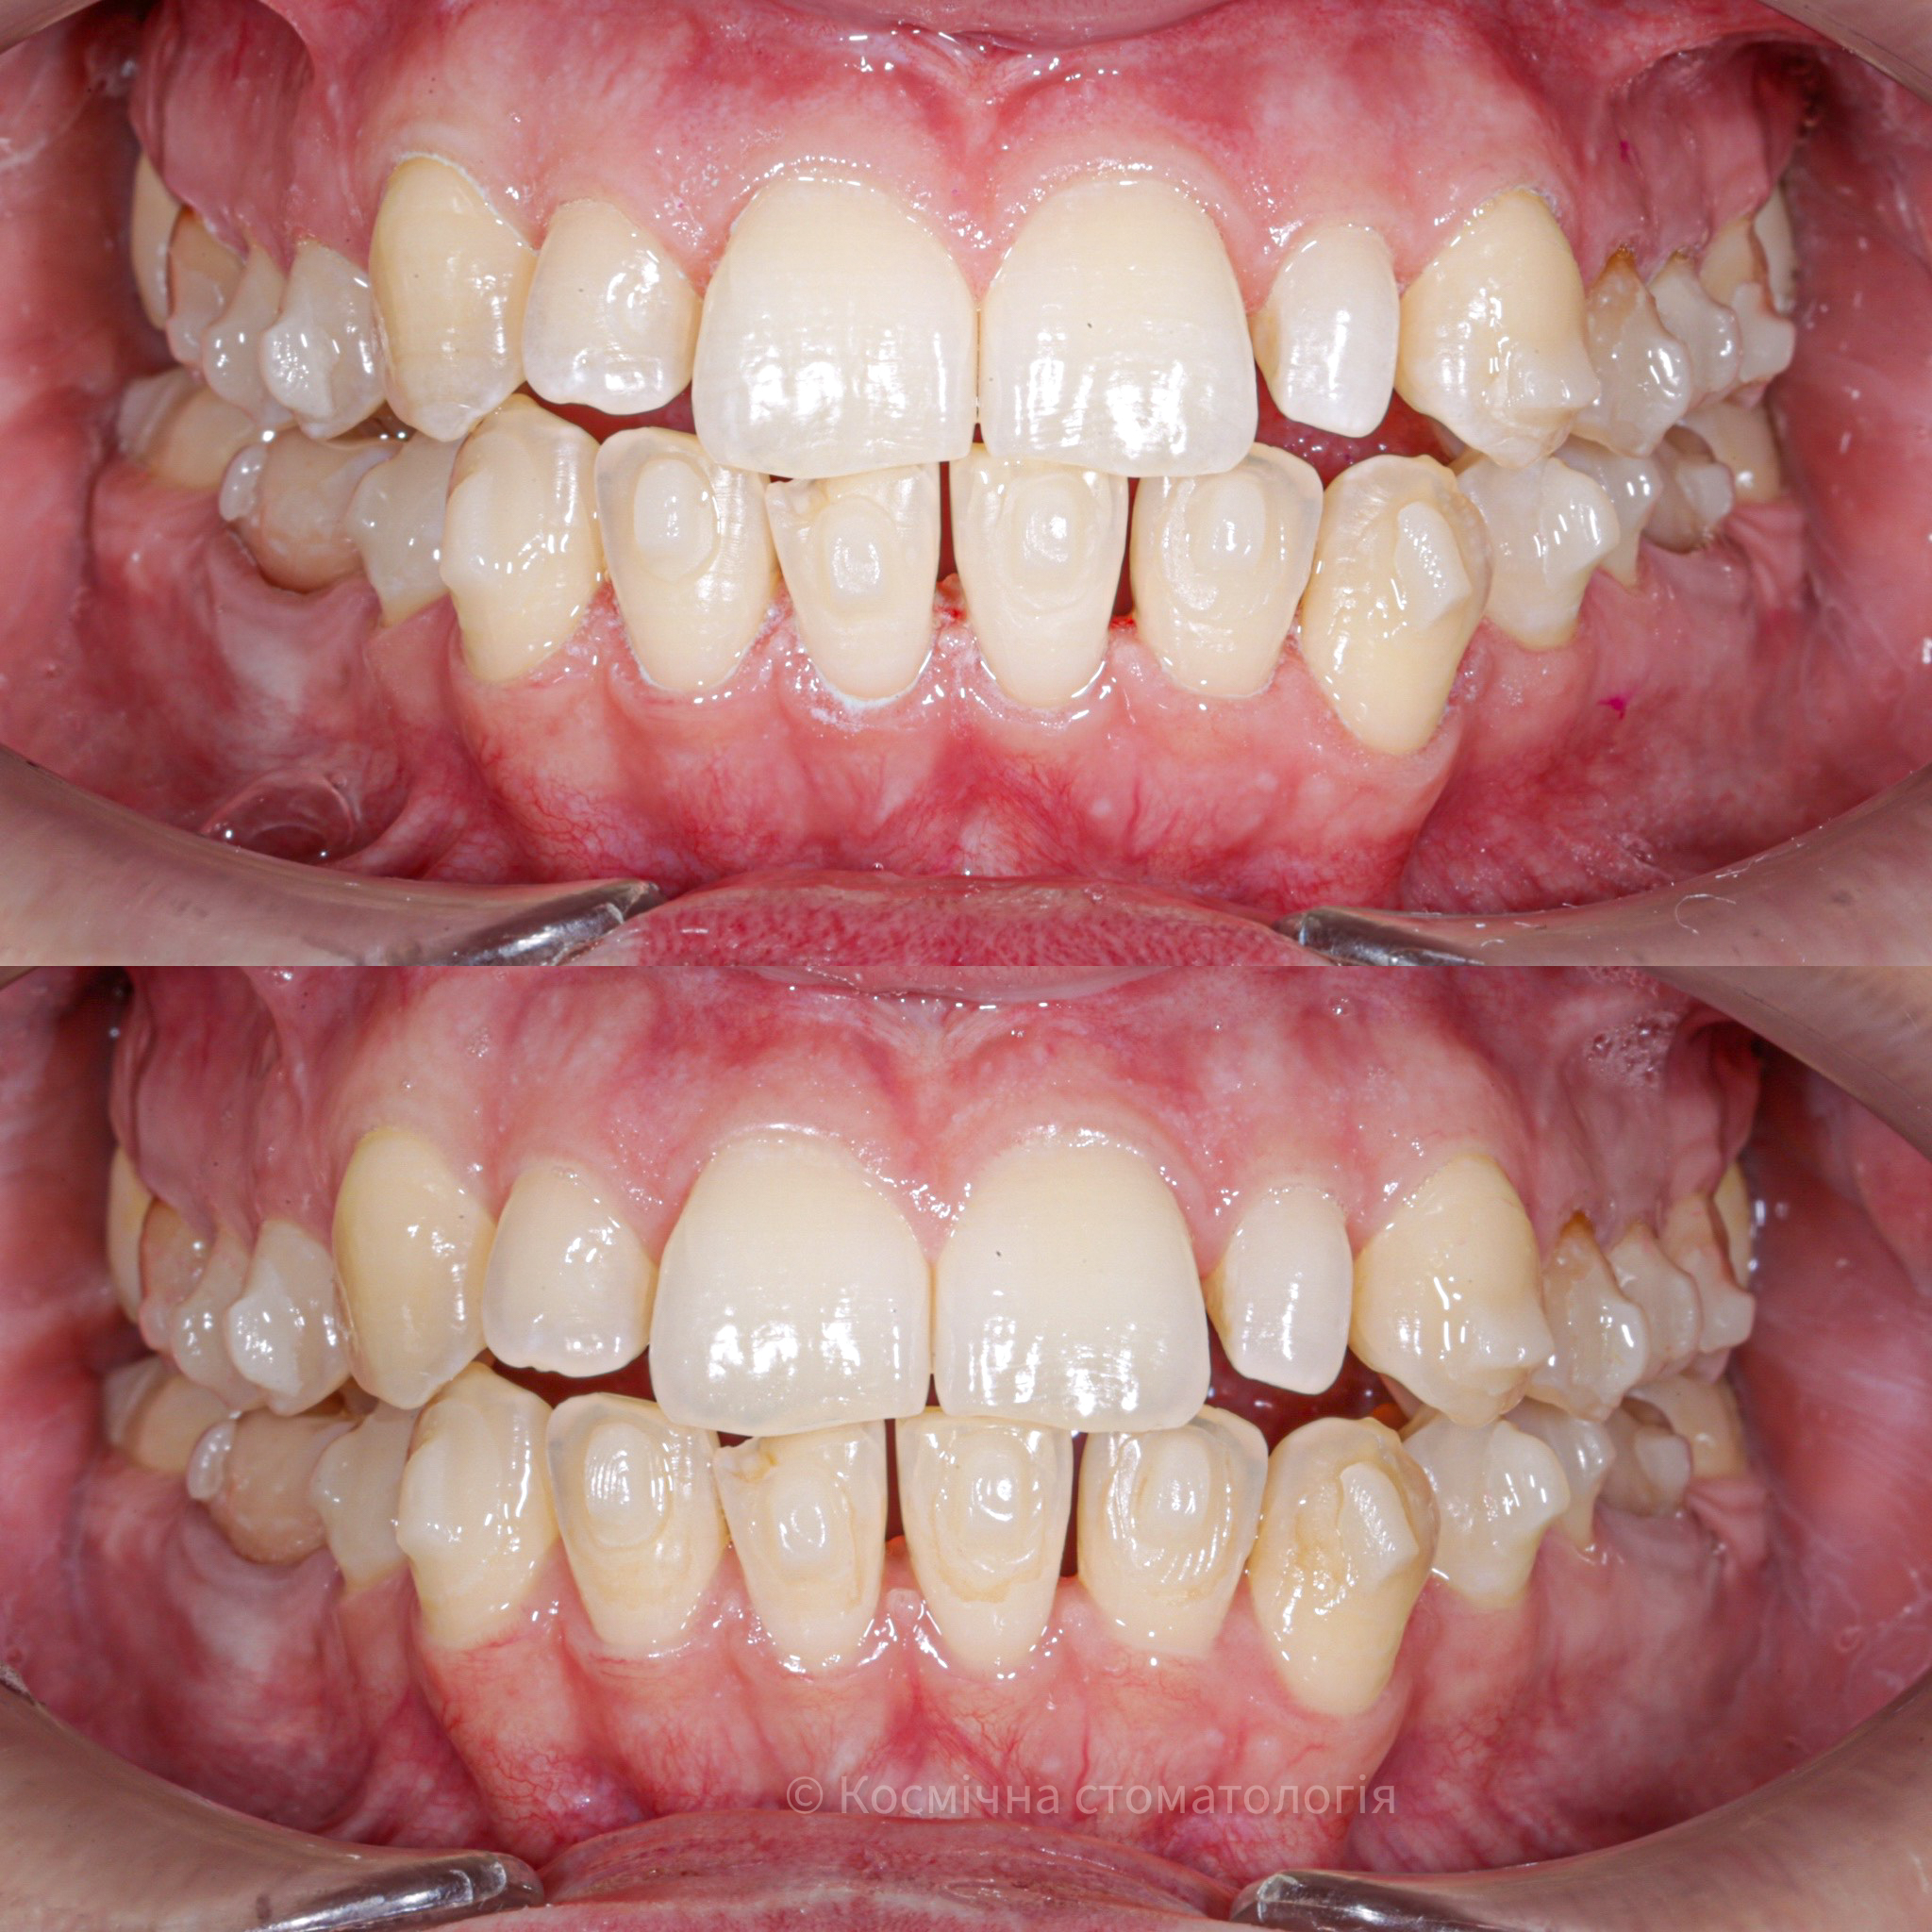

Галерея

Професійна гігієна (чистка) зубів складається з кількох етапів

• Комп'ютерна анестезія у разі підвищеної чутливості зубів.

• Зняття каменю ультразвуковим девайсом SIRONA (Німеччина) та звуковим наконечником KAVO (Німеччина) з електронним регулюванням потужності.

• Зняття каменю у важкодоступних місцях пародонтальними кюретами HU-Friedy.

• Зняття нальоту гігієнічними перлинами KaVo PROPHY pearls SUPRAGINGIVAL CALCIUM CARBONATE в індивідуальних пакуваннях із ароматом на вибір: персик, апельсин, м'ята, чорна смородина та нейтральний смак.

• Полірування швейцарською пастою Proxyt Ivoclar Vivadent для блиску та природної білизни.

• Діагностика прихованих захворювань ясен (скрінінг-тест).

• Покриття зубів фтористим лаком у місцях підвищеної чутливості;

• Ремінералізуюча терапія;

Повітряно-абразивна чистка зубів (Air Flow)

Завдяки піскоструменевому апарату з технологією Air Flow, який використовуючи тиск повітря та води, подає на зубну емаль спеціальний абразивний склад, зуби можна очистити не лише від м’якого нальоту, а й від пігменту. Для видалення нальоту, в Космічній стоматології Драганчука ми використовуємо KaVo prophy pearls supragingival calcium carbonateneutral.

Чистка зубів щіточками та пастами

Фінальний етап професійної гігієни - полірування спеціальними щіточками та пастою, щоб усунути мікротріщини та шорохуватості, що виникли після чистки та видалити залишки нальоту, що могли в них залишитись. Це дозволяє суттєво уповільнити формування нових відкладень.

Полірування зубної емалі гумками

Кінцеве полірування поверхні зубів проводиться із застосуванням різних насадок, зокрема спеціальних гумок, що надає зубам ідеальної гладкості та блиску. Спеціальні гумові насадки відмінно справляться з наданням естетичної довершеності твоїй посмішці.